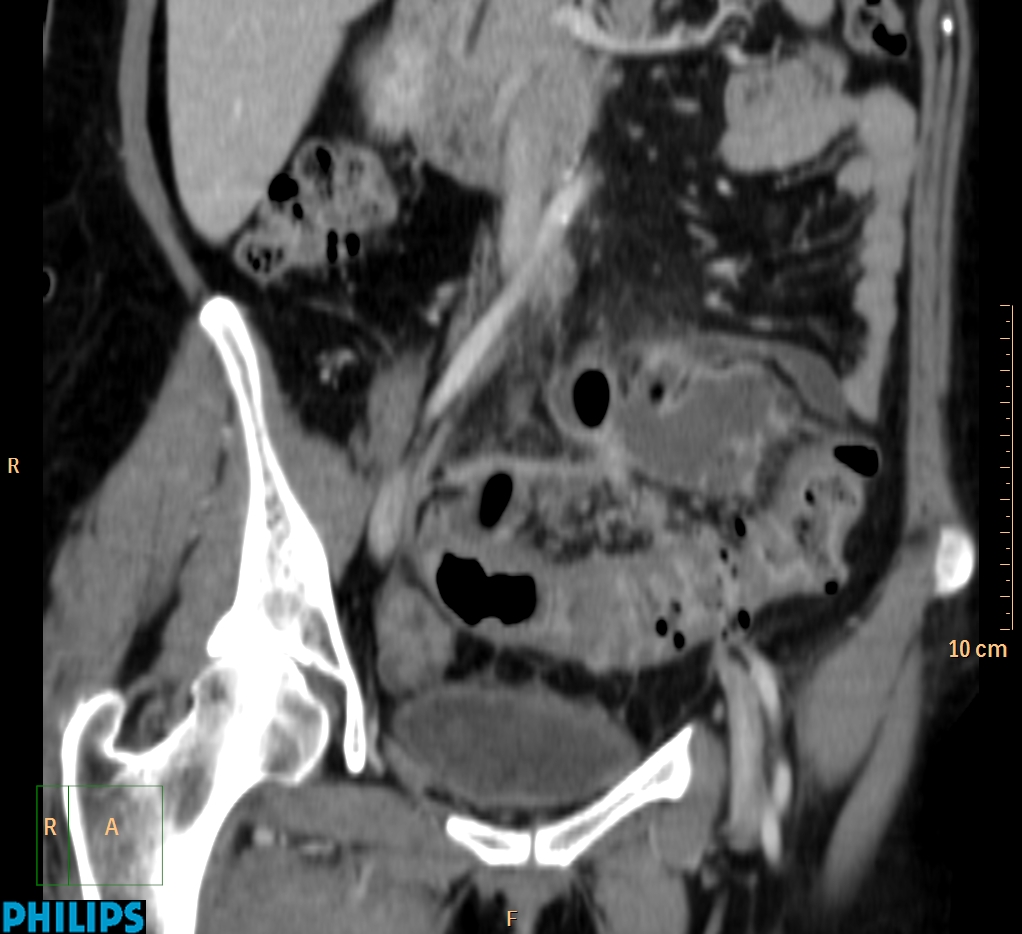

ΕΚΚΟΛΠΩΜΑΤΑ ΠΑΧΕΟΣ ΕΝΤΕΡΟΥ Posted by ΙΠΠΟΚΡΑΤΕΙΟ ΙΩΑΝΝΙΝΩΝ | Dec 16, 2020 | ΠΕΠΤΙΚΟ | 0 ΚΛΙΝΙΚΑ ΣΤΟΙΧΕΙΑ – ΙΣΤΟΡΙΚΟ υποτροπιάζοντες επαναλαμβανόμενοι πυρετοί κυρίως απογευματινές ώρες ΕΡΓΑΣΤΗΡΙΑΚΟΣ ΕΛΕΓΧΟΣ ΑΠΕΙΚΟΝΙΣΤΙΚΟΣ ΕΛΕΓΧΟΣ διακρίνονται τα αποστήματα στην ελάσσονα πύελο, καθώς και εκκολπώματα με εικόνα πάχυνσης του τοιχώματος του σιγμοειδούς ΣΥΖΗΤΗΣΗ